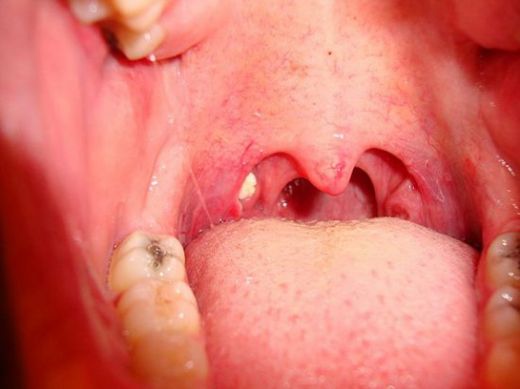

- Cerrahi müdahale: Tekrarlayan bademcik iltihabı durumunda, bademciklerin cerrahi olarak alınması (tonsilektomi) düşünülebilir.

Dikkat Edilmesi Gerekenler

Tek taraflı bademcik şişmesi, bazen daha ciddi durumların bir belirtisi olabileceğinden, doktorun önerilerini dikkatle takip etmekte fayda var. Özellikle ateş, şiddetli ağrı veya nefes alma zorluğu gibi belirtiler varsa, derhal sağlık kuruluşuna başvurmak gerekebilir.

İyileşme Süreci

Umarım en kısa sürede tedavi sürecin başlar ve en kısa zamanda sağlığına kavuşursun. Bol sıvı almayı, dinlenmeyi ve doktorunun önerdiği tedavi yöntemlerini uygulamayı unutma. Kendine iyi bak!